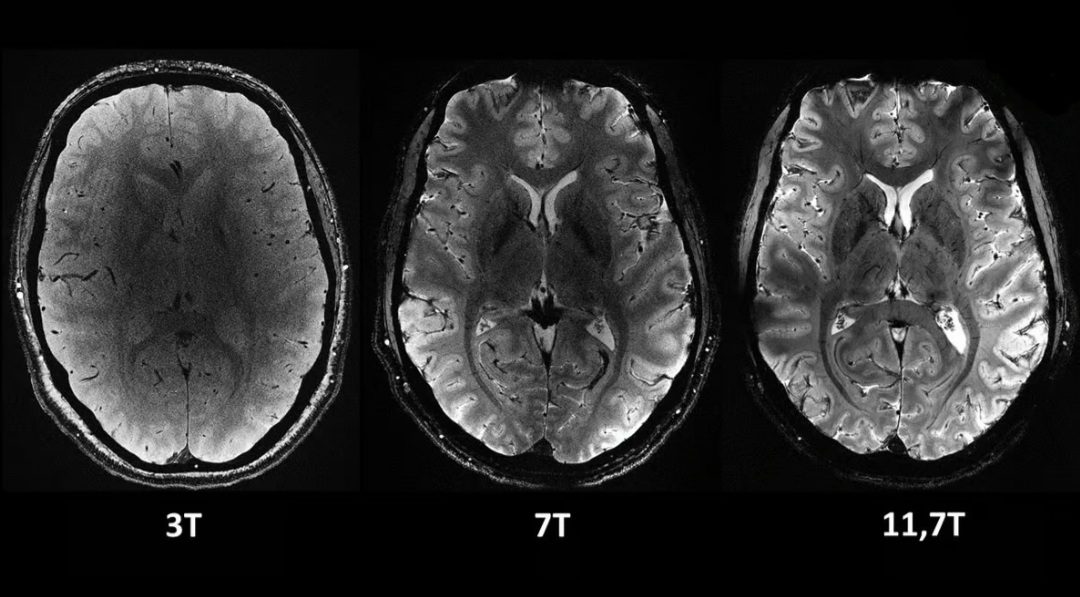

دستگاه Iseult MRI که توسط کمیسیون انرژیهای جایگزین و انرژی اتمی فرانسه (CEA) توسعه یافته است، دارای قدرت میدان مغناطیسی 11.7 تسلا (T) است. در مقایسه، دستگاههای MRI معمولی که امروزه در بیمارستانها به طور گسترده مورد استفاده قرار میگیرند، معمولاً 1.5 یا حداکثر 3 T هستند.

تصاویر مقایسه ای از مغز انسان که با دستگاه جدید Iseult MRI در سطوح مختلف قدرت گرفته شده است. همه این تصاویر در مدت زمان یکسانی گرفته شدهاند و نشان میدهد که چقدر میتوان جزئیات بیشتری را با آن گرفت.